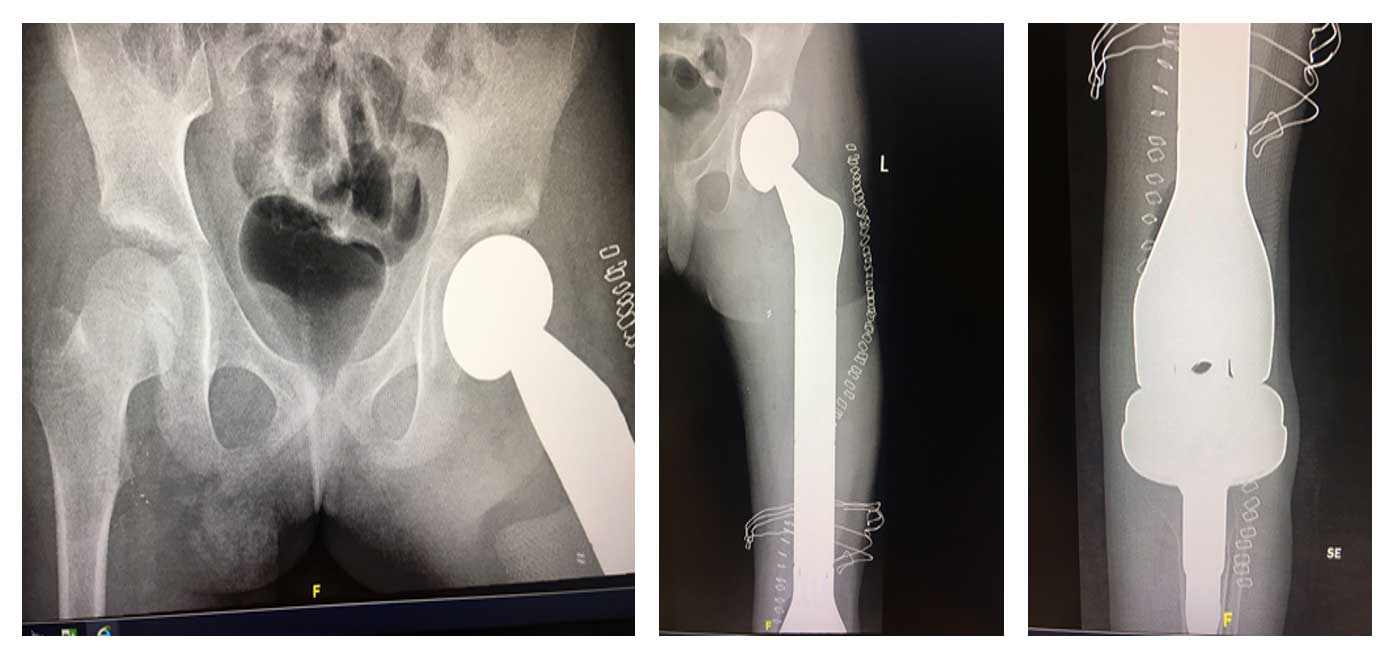

Ameliyat Sonrası: Röntgende total femur protez uygulanımı görülmekte.